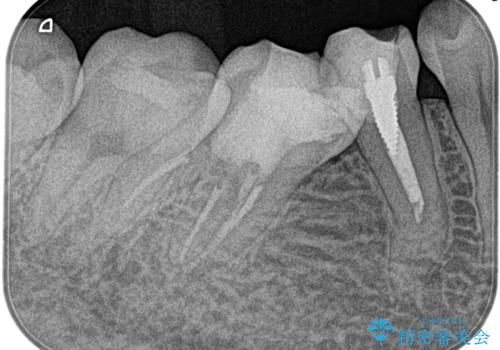

【湾曲根管】奥歯がズキズキ痛い

- 奥歯が1週間前からズキズキ痛いことを主訴に来院されました。

診査の結果、不可逆性歯髄炎と診断し抜髄処置を行っております。

【使用ファイル】NEX-MS

【充填法】Hydraulic Condensation